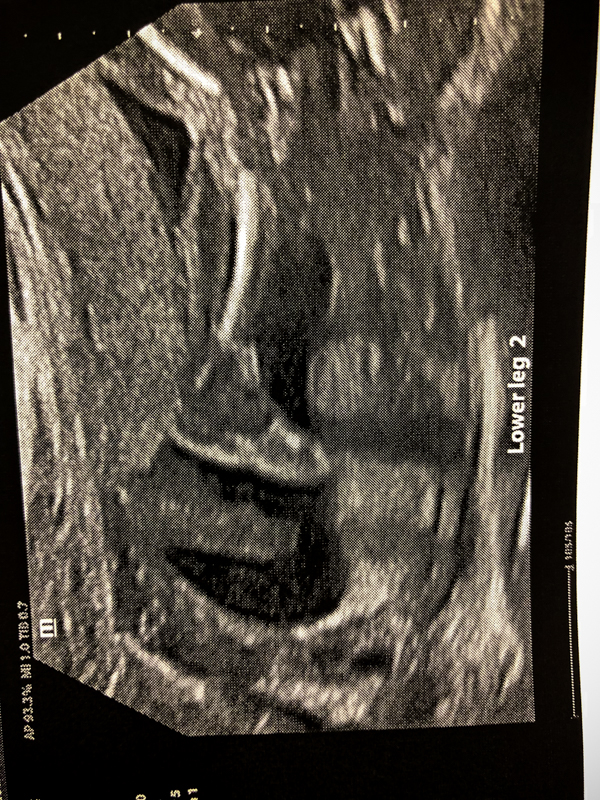

Baby B (which stands for Baby Brother, Baby Boy, Baby B versus Baby A) was wiggling around a lot in there. He was in a pike position with his hands shooting out in front of him nearly touching his toes! We weren’t able to get a good profile pic, but look at this leg!